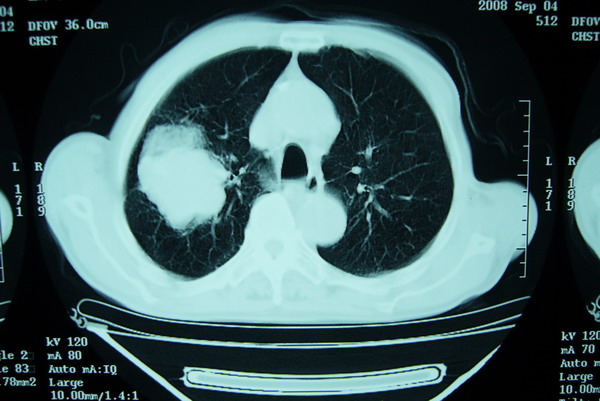

标题: CT15579:男 86岁 咳嗽 咳少量白痰 发热2天 吸烟史60年 [打印本页]

标题: CT15579:男 86岁 咳嗽 咳少量白痰 发热2天 吸烟史60年

右上周围型肺癌,慢支,肺气肿。

分叶及少量边缘性钙化,老年人,周围性肺癌首先考虑。

右肺上叶巨大软组织肿块,轮廓不规则,纵隔内有肿大淋巴结,首先考虑肺癌。

右上肺一不规则团块,边缘有分叶和毛刺,纵隔有淋巴结肿大。右肺周围性肺癌首先考虑。